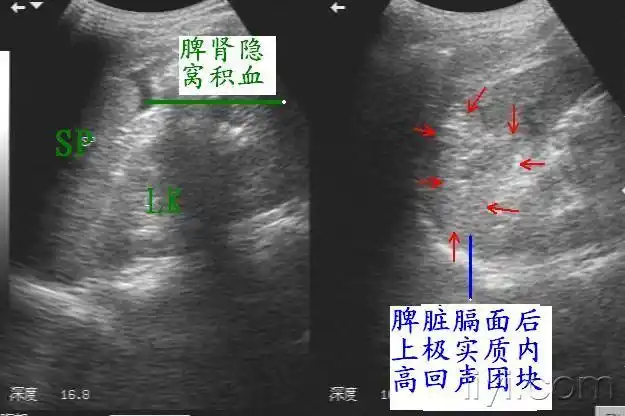

迟发性脾破裂(10月4日更正) - 超声医学讨论版 - 爱爱医医学论坛

脾脏超声诊断